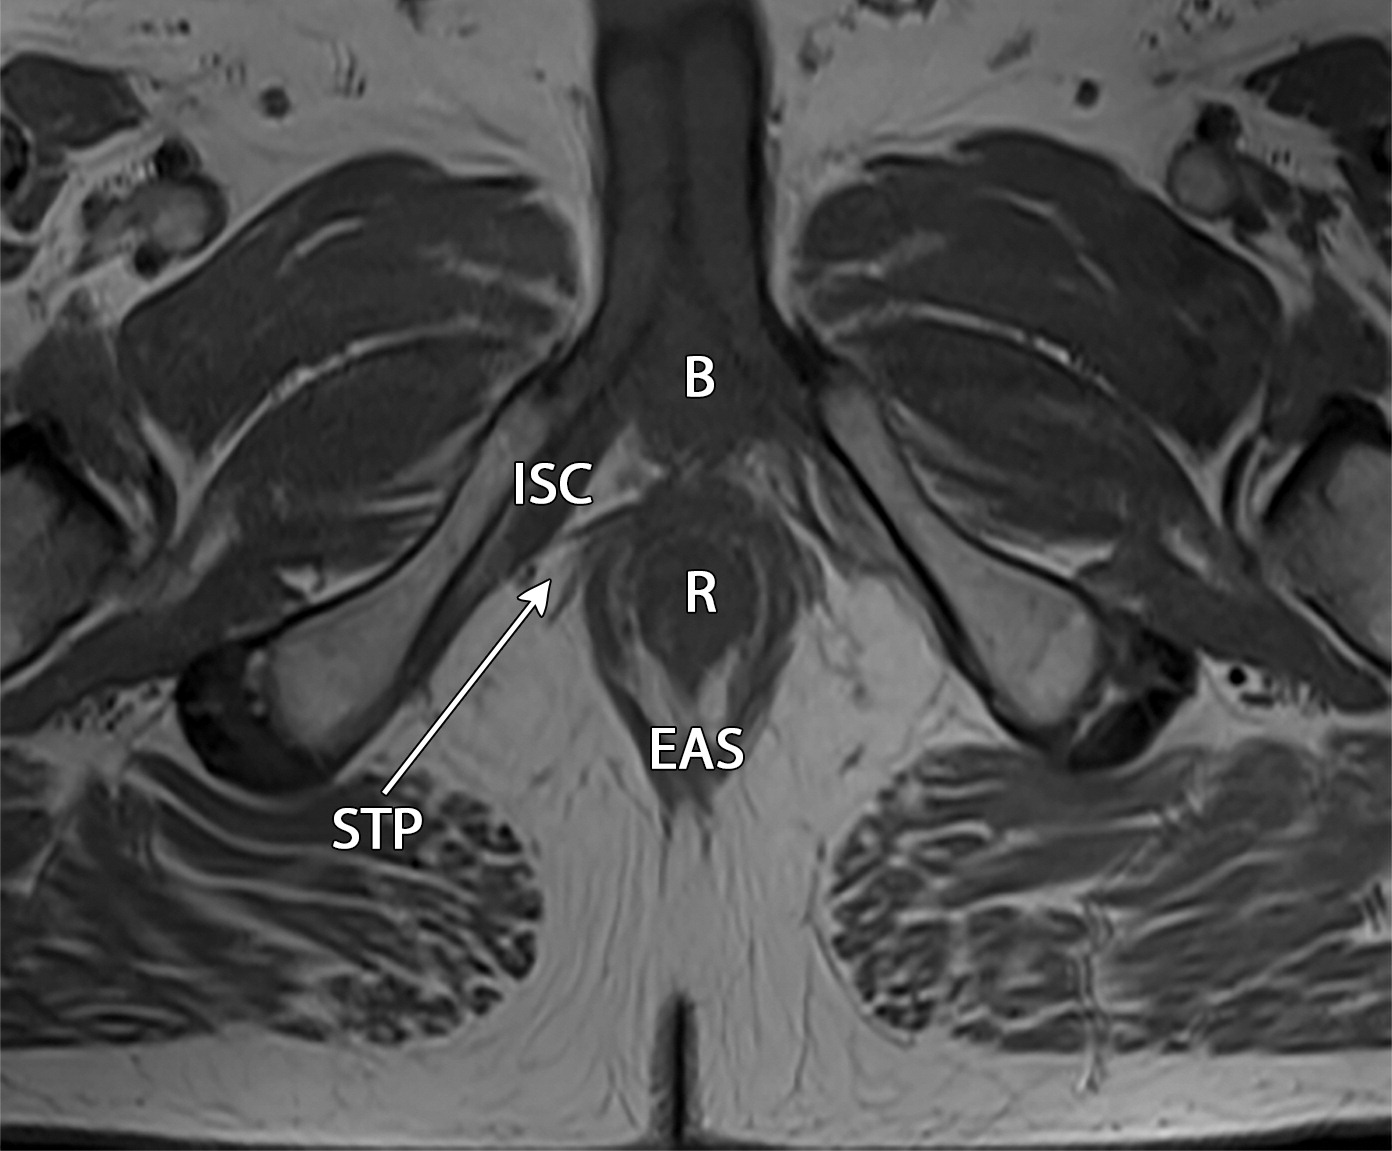

50岁以上男性骨盆和盆底的MRI解剖。

提肛肌(LA),由耻骨直肠肌(PR)、耻骨尾骨肌(PC)和髂尾骨肌(IC)组成;尾骨肌(C),前列腺(P),闭孔内肌(OI),会阴浅横肌(STP),球海绵体肌 (B), 坐骨海绵体肌(ISC),肛门外括约肌(EAS),肛门内括约肌(IAS),直肠(R),尿道括约肌(SU),也称为尿道外括约肌(U),它包围着整个膜性尿道。6774449af17bb1b8df6e83ab4e9fa158.jpeg